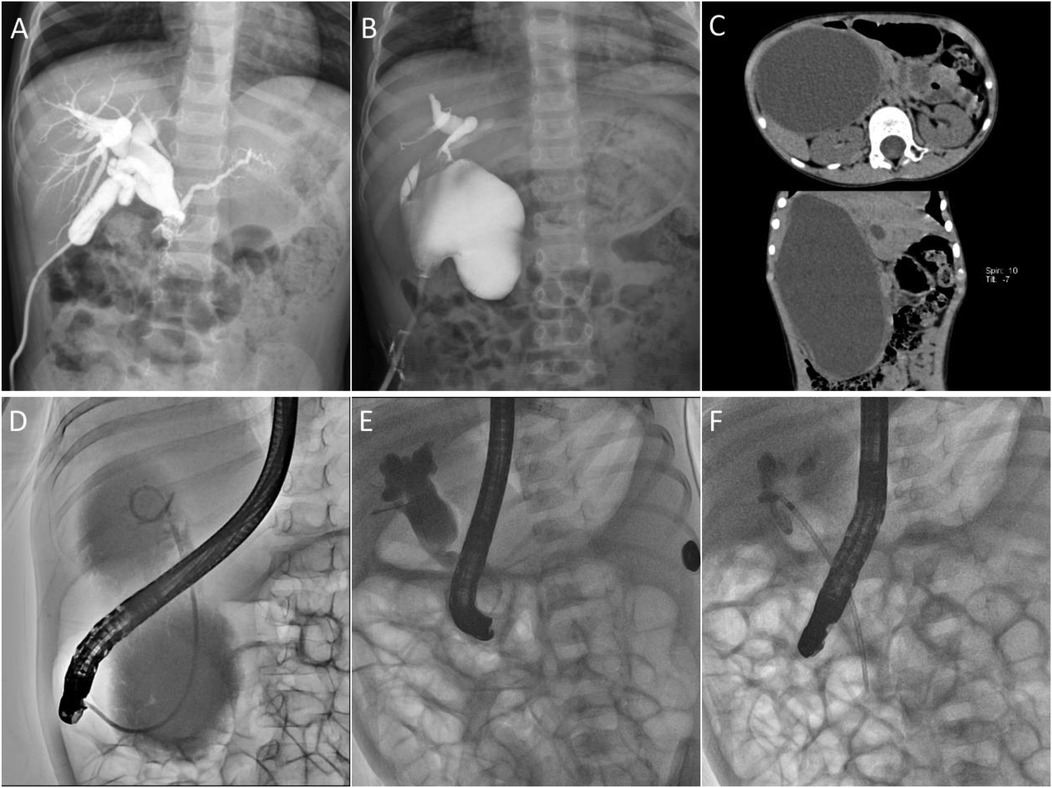

Figure 2. Imaging findings of different drainage modalities. (A) Laparoscopic external drainage of the gallbladder; (B) Laparoscopic external drainage of the bile duct; (C,D) A 5-year and 7-month-old child with a substantial common bile duct associated with severe cholangitis underwent EBD. (C) CT image indicated that the cysts were huge, and the size of the cysts was about 16 × 10 cm. (D) Under fluoroscopic guidance during ERCP, a 7-French nasobiliary catheter was selectively positioned within the cyst to establish continuous biliary decompression, and the cysts shrunk to 4 × 3 cm three weeks after the operation. (E,F) Under fluoroscopic ERCP guidance, a 7 Fr–7 cm pancreatic duct stent was placed reversely for internal biliary drainage.

EBD group

The child was placed in a prone position under general anesthesia. A duodenoscope (JF-260 V, 11.3, and 3.7 mm operative channel or TJF-260 V, 11.3, and 4.2 mm operative channel; Olympus, Tokyo, Japan) was advanced to the duodenal papilla. Using a guidewire-assisted technique, a papillotomy knife (Anrei, Hangzhou, China) was introduced, followed by selective bile duct intubation and cholangiography to confirm the biliary anatomy. A guidewire (Anrei, Hangzhou, China) was then inserted into the bile duct, and either a nasobiliary drainage tube (Cook, Limerick, Ireland) or a stent was advanced along the guidewire into the cyst for bile drainage (Figures 2D–F). Due to the unavailability of pediatric biliary stents, pancreatic duct stents (7Fr–7 cm; Cook, Limerick, Ireland) were used for ERCP-guided endobiliary drainage (Figure 2F). All equipment used was originally designed for adult ERCP procedures.